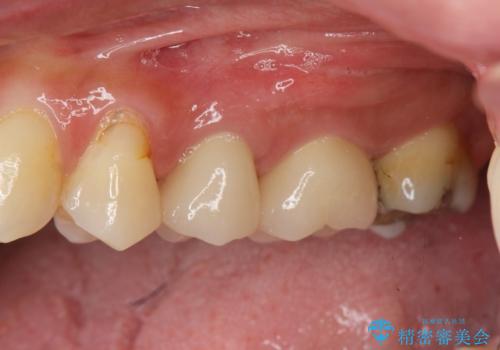

放置し崩壊した歯 セラミック治療による咬合機能回復

虫歯を丁寧に除去したのち、なんとか歯を残せる見通しがたったので根管治療を行いセラミック補綴を行いました。

- 24万円(仮歯×2・ファイバーコア・ジルコニアクラウン×2)費用は治療当時の料金となります